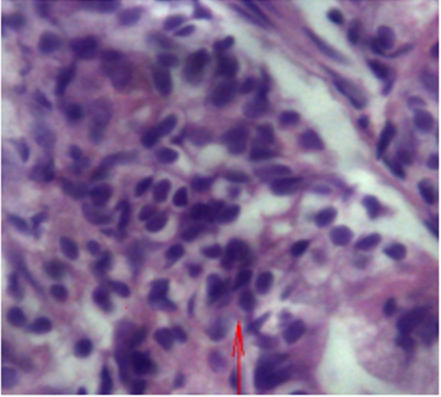

з) Больной, 10 лет Хронический аутоиммунный гастрит с начинающейся деструкцией желез. Увеличение x 400. Окраска гематоксилин-эозин.